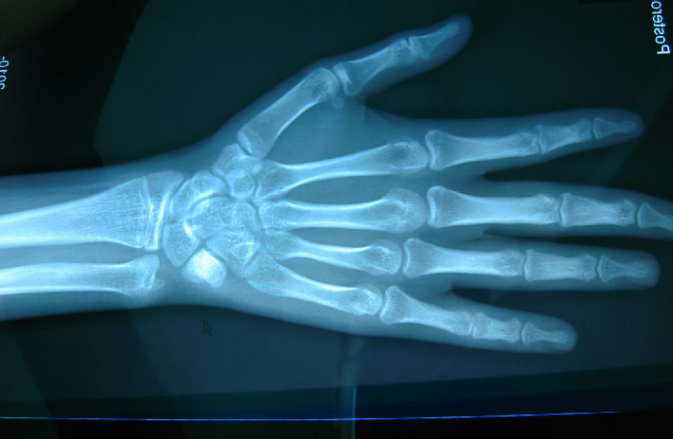

2、什么是骨龄及骨龄标准

骨龄,通俗点说就是我们骨骼的年龄,它之所以可以被用作判断人体成熟度的标准是因为它在很大程度上代表了小朋友们真正的发育水平,相比较实际年龄要更加准确。

在人体的发育过程中,骨头的发育是有两个特点的:连续性、阶段性,并且在发育过程中的变化基本上也具有相似之处。只是处在不同阶段的时候,形态可能会有所不同,这也是为何骨龄评估能更加确切地显示出每个人的生长发育水平和成熟程度的原因。对于大多数人来说,骨龄评估有4个作用:确认小朋友在生物学意义上的年龄,帮助家长们早一些知晓自家小朋友的生长潜力和未来身高走势;预判小朋友成年后的身高情况;帮助医生发现一些儿科内分泌疾病的出现;在治疗身材矮小的患者时,给医生提供参考和指导。